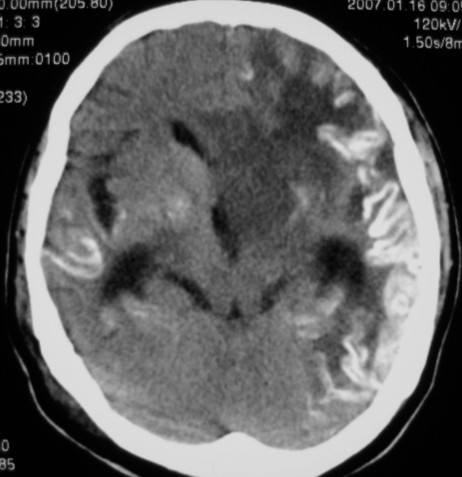

标题: CT9218:男性,50岁,脑出血术后复查,两次片相隔半月,请分 [打印本页]

标题: CT9218:男性,50岁,脑出血术后复查,两次片相隔半月,请分

第一次ct片脑出血术后,出血吸收期。第二次ct 片左颞顶枕部及右颞顶部有脑回样高密度影。考虑珠网膜下腔出血。脑出血术后改变,脑出血恢复期 并脑积水。

是蛛网膜下腔出血么?蛛网膜下腔出血应该在脑沟里,而此高密度影是沿脑回分布,应该是脑膜感染后钙化灶形成。

应该是脑膜感染后钙化灶形成。脑出血术后改变;脑积水

应该是脑回钙化,不是出血

考虑是脑回钙化,不是出血,什末样的蛛网膜下腔出血是这样的?我没见过!考虑脑炎性钙化,要结合病史!